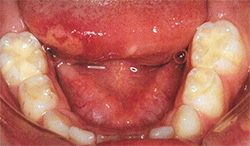

歯肉嚢胞(上皮真珠)

- [好発年齢・性差]

- 新生児あるいは乳児期

- [好発部位]

- 歯ぐきや上あごの天井(口蓋)にみられる。

- [症状]

- 白から乳白色の丸い粒で、直径は1〜3mm程度である。1個から数個のこともあれ ば、数個集まって歯ぐきがデコボコしてみえることもある。 原因としては、赤ちゃんがお腹の中で成長する際、歯や口の組織が作られる過程で 余った組織の成分(上皮細胞)が吸収されずに残り、角質化したものである。

- [治療]

- 痛みはなく、 赤ちゃんが痛がったり、ミルクが飲めなくなったりすることはない。数週間から数ヶ月で自然に剥がれ落ちたり、吸収されたりして消えてしまうため、治療の必要はない。気になって指やガーゼでこすり取ろうとすると、デリケートな粘膜を傷つけ、細菌感染の原因になるため、そのままにしておく。